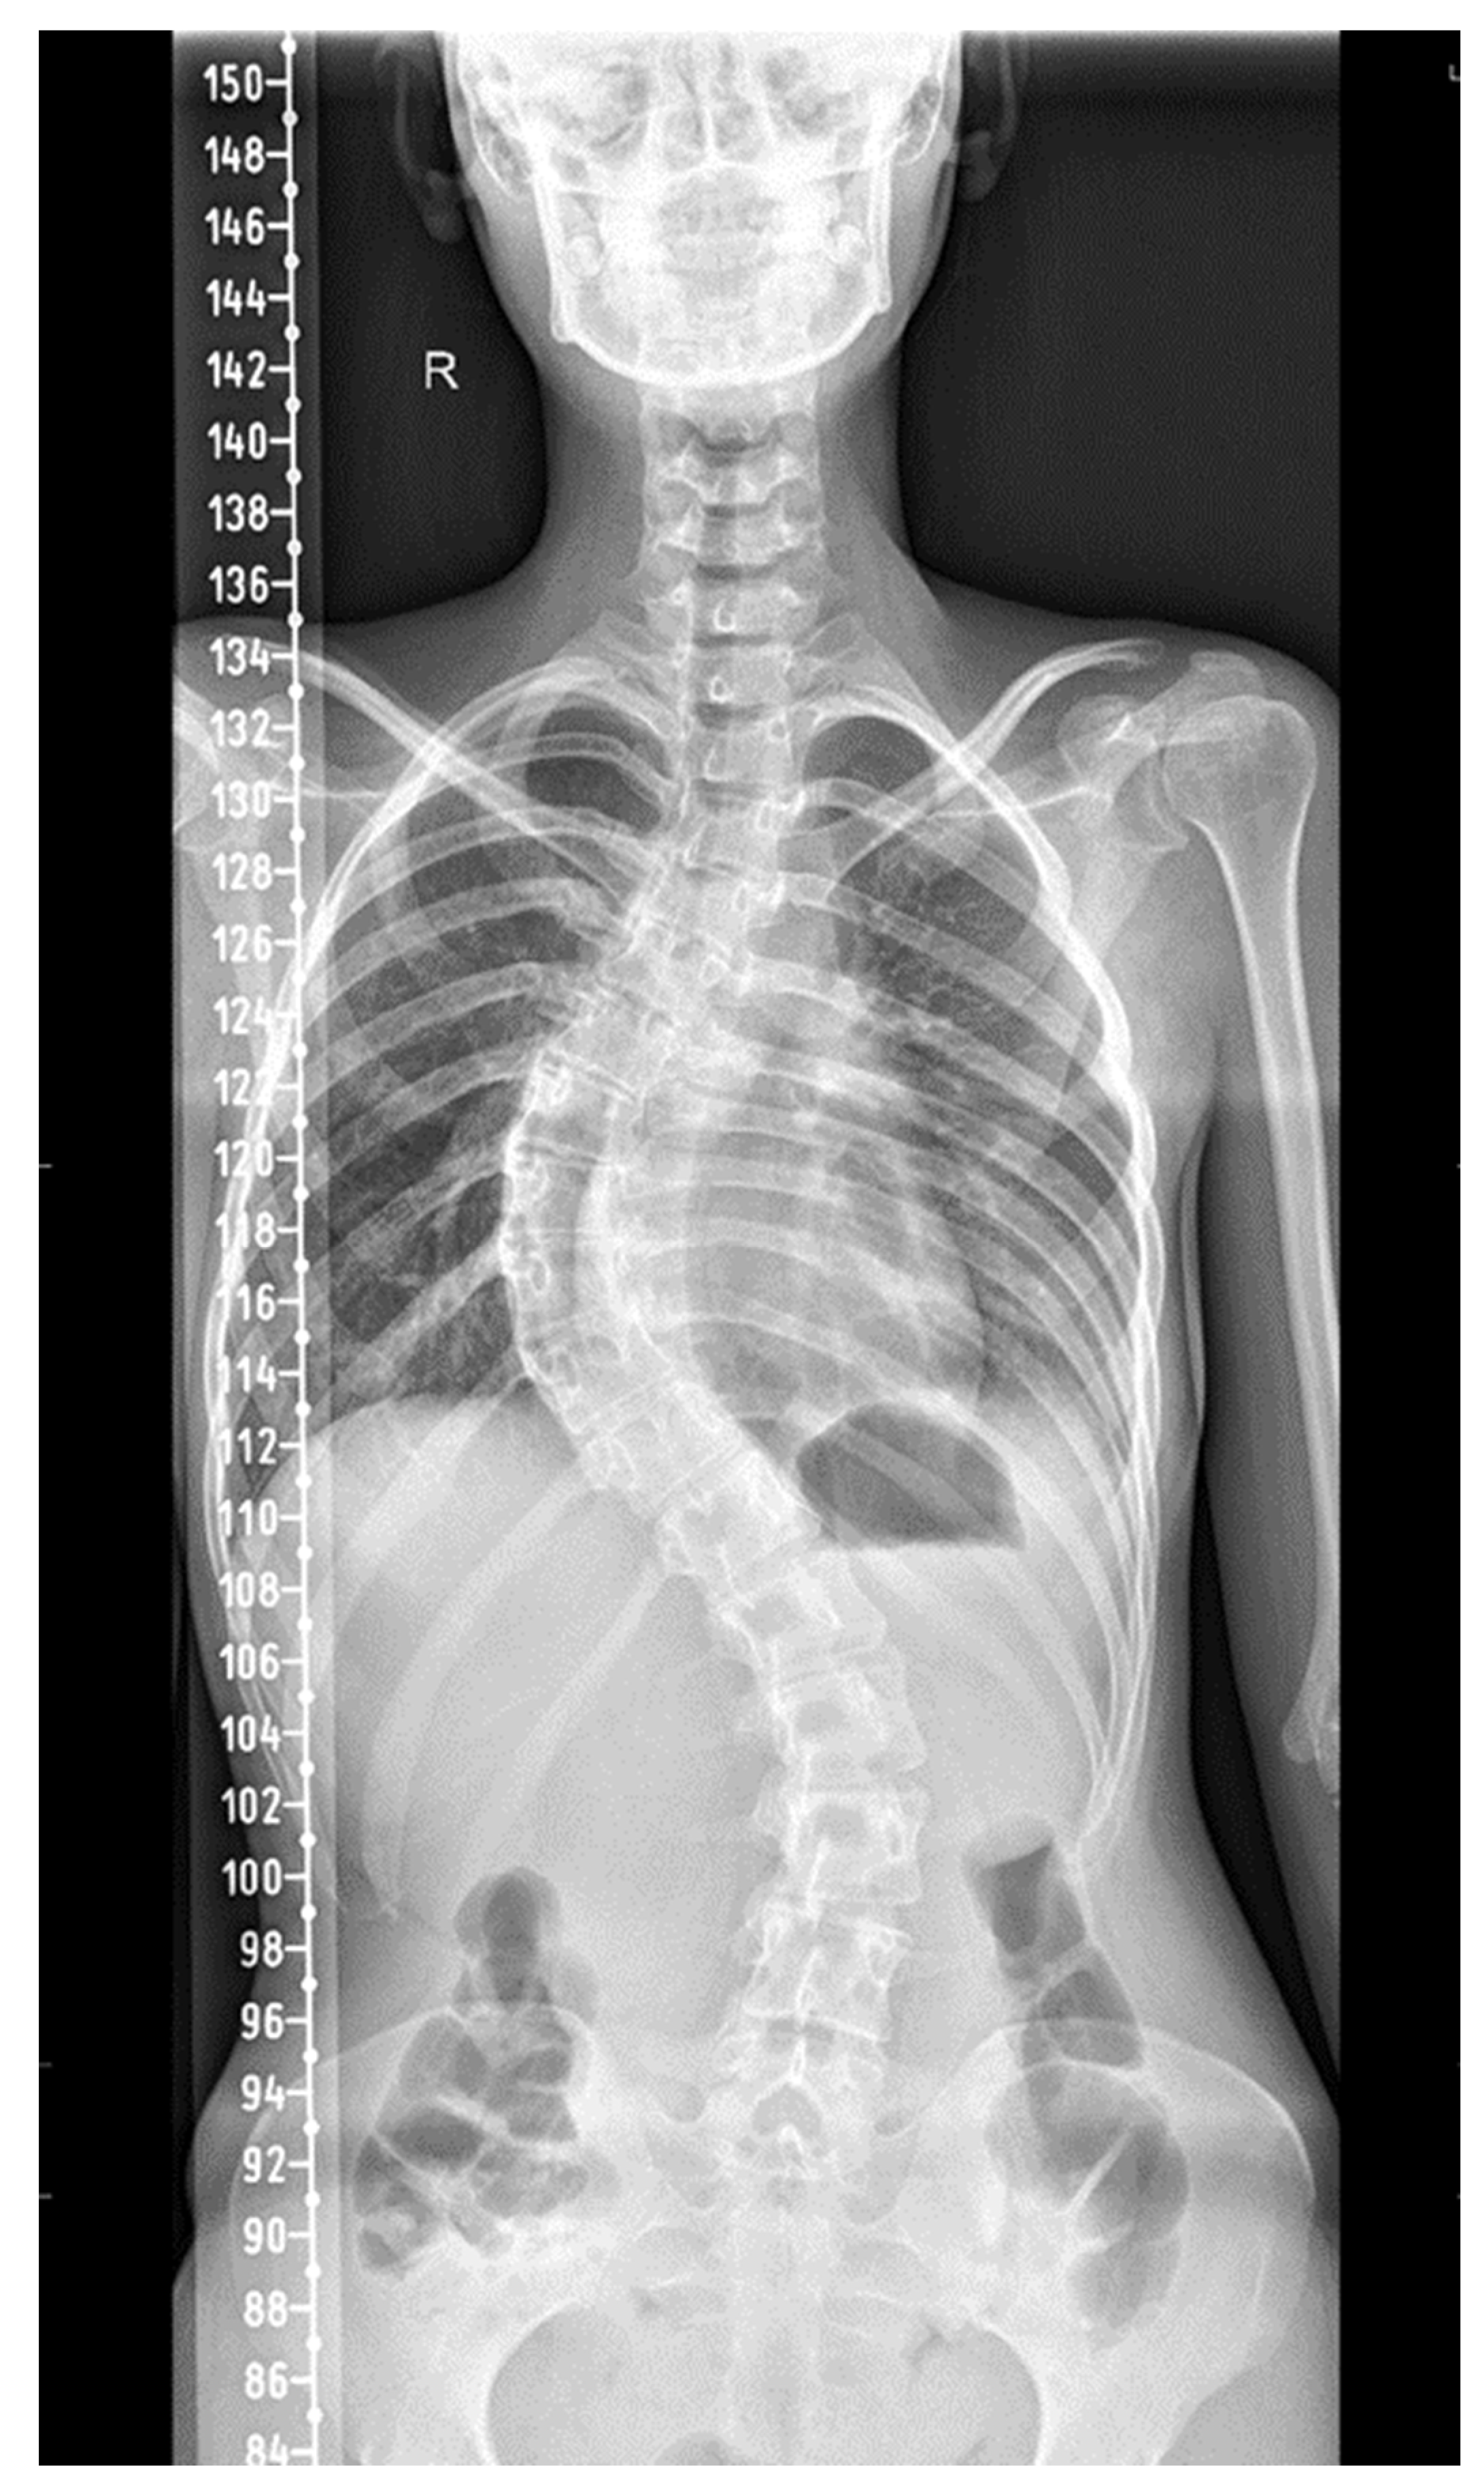

| Skeletal | Rib cage deformities due to stiffness, scoliosis, respiratory muscle weakness | Orthopedic surgeon and pulmonary specialists’ evaluation |